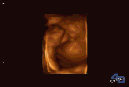

超声影像(四维彩超),到底查什么?

而超声影像(四维彩超)是筛查胎儿面部、肢体、内脏等器官发育畸形。